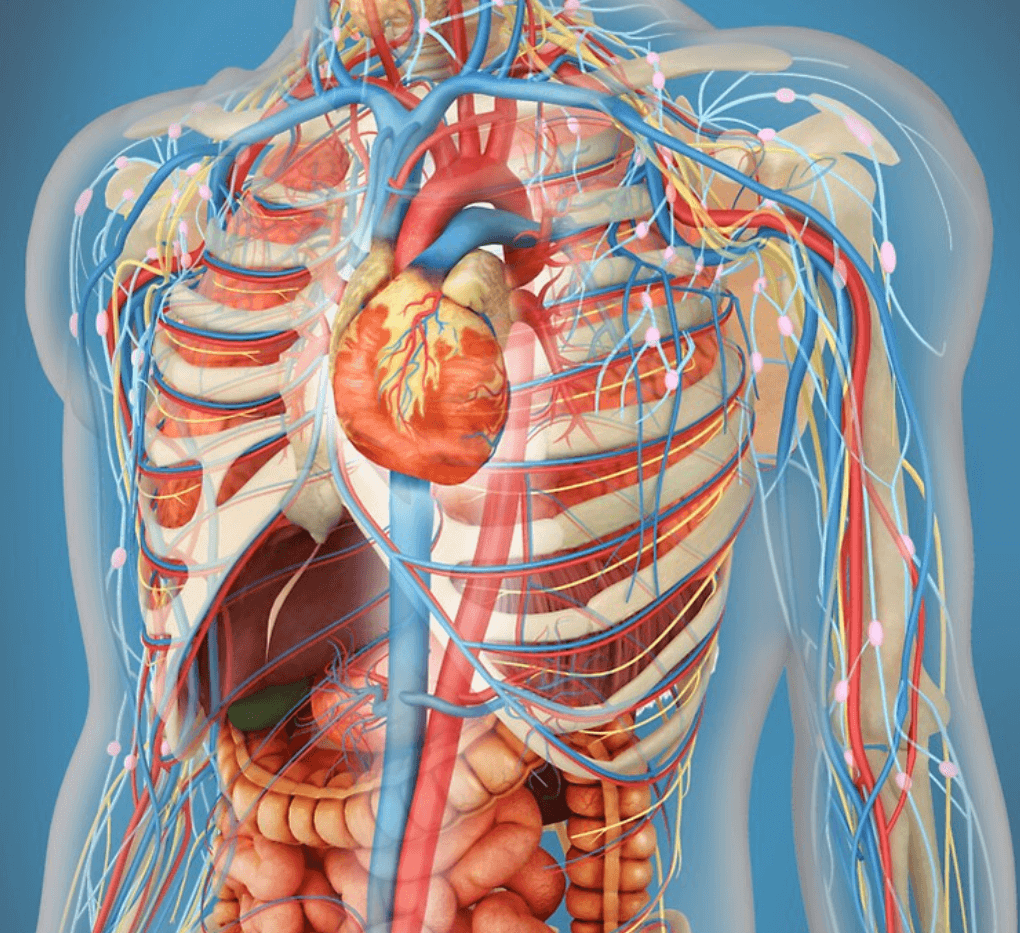

Изображения и визуализация внутренних органов человека